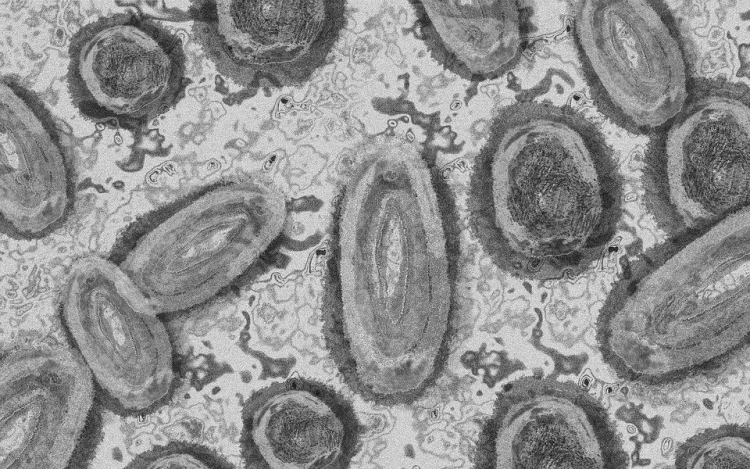

Megfertőződött majomhimlővel egy négyéves kislány Németországban - jelentették kedden német hírportálok az országos közegészségügyi intézet (RKI) adatai alapján.

Németországban első alkalommal mutatták ki a kórokozót gyermek szervezetében.

Az Afrika egyes részein évtizedek óta ismert és ritkán előforduló majomhimlő május óta Európában, Észak-Afrikában és más térségekben is terjed. Az Egészségügyi Világszervezet (WHO) júliusban globális egészségügyi vészhelyzetnek nyilvánította a járványt.